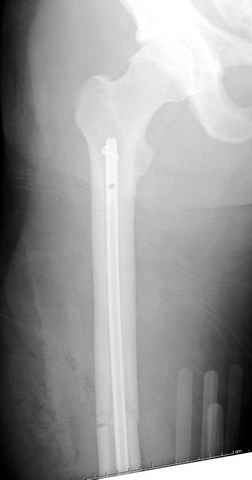

больному 42, автоавария, политравма, открытая черепномозговая травма, безсознании, открытый перелом бедра, размозжение мягких тканей, дефект кожи на передней поверхности бедра около 13 см2 от ожога, компартмент синдром.

По поводу открытого перелома больной ургентно взят на ретроградное интрамедулярное штифтование, после рутинного дебрайдмента и фасциотомии на бедре и на голени.

перелом бедра